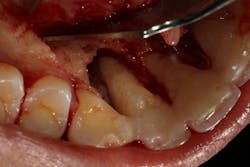

Another scenario that took place in a private practice with actual dollar amounts can be seen in treatment plan C. This patient had already paid for treatment plan B in the $5,000–$7,000 range and subsequently presented to the practice with moderate peri-implantitis. In addition to the money the patient had already invested, she would now be responsible for the financial costs of treatment plan C.

After reviewing the additional costs and lengthy healing time involved with surgery to correct the ailing implant, the overall costs associated with treatment were in the $8,000–$10,000 range, with more than three years of treatment time invested. Of important note is that most insurance companies limit the amount of reimbursement for implant-related services. When dealing with insurance companies, accurate ADA coding and claims submission are critical to facilitate services and expedite reimbursement.